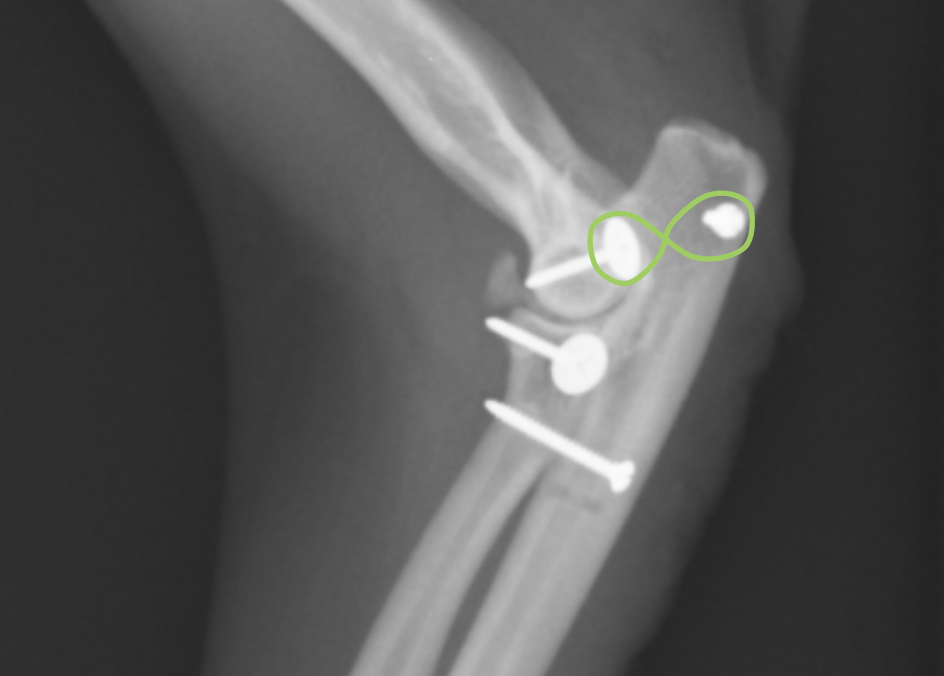

次に上腕骨と橈骨を結ぶ側副靭帯を再建します。アンカーと呼ばれるスクリューをうち、そこに黄色で書いた位置に人工靭帯を結びます。

最後に上腕骨と尺骨を結ぶ靭帯を再建します。実際にはこのような靭帯は存在しませんが、ここを締結することで脱臼しにくくなります。

最終的なX線画像です。ずれていた橈骨尺骨上腕骨がピッタリとあっているのが分かると思います。小さな骨片が見られますが、ここの脱臼の場合このような小骨片がかけてしまうことがよくあります。